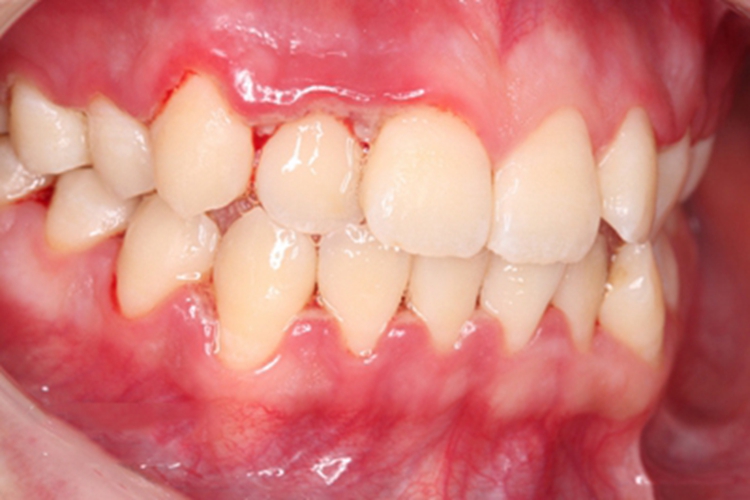

急性坏死性溃疡性龈炎起病急,病程短,常为数天至1-2周,初起时牙龈肿胀、充血,个别牙龈处可发生坏死性溃疡,表面覆有灰白色坏死物,中央凹下如火山口状,可伴有出血。